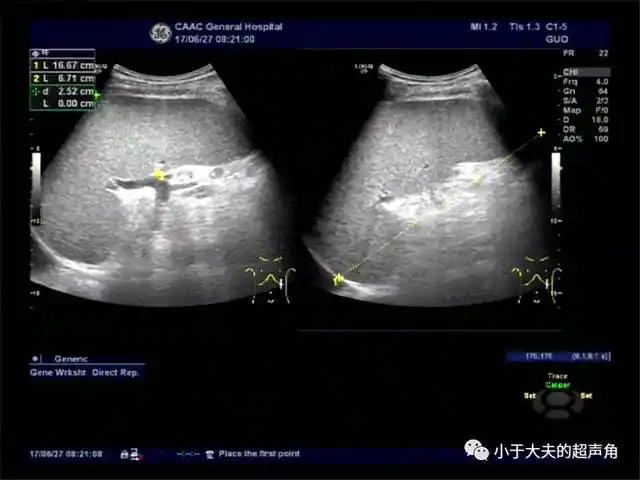

发现上腹部胰腺周围及腹主动脉旁数个异常肿大淋巴结,及肿大的脾脏